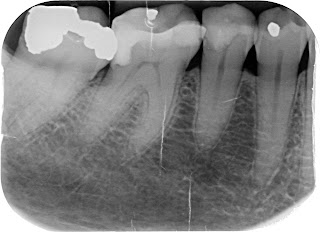

It being Waitangi weekend it was really difficult to find an emergency dentist. After many dead ends I found one in Hornby, Goodbye to $1050. Simple Xrays were taken, an impression made and I was required to make a major decision on the spot. To have a permanent plate and all the awkwardness and inconvenience that entailed or to have a temporary one that could only look OK as a smile-saver. I instantly had to consider the long-term options.

I sent the Xrays off to JC and asked his opinion on the best solution. We both felt that an implant was the only reasonable solution but the cost was way beyond my resources. JC offered to pay the cheapest estimate, bless him, though I told him he is no longer responsible for me. His generosity relieved a bit of the stress but the consultation with the surgeon since then has added more stress as he informed me I'd need to pay at least $1000 more than the dentist had told me. I am not sure how I will find that.

The consultation with the surgeon takes the form of lots of waiting, high-tech xrays which are effectively 3-D modelling, information on current medications, checking bone quantity and density, preferences for anaesthesia and confirmation that I am happy to proceed, signing a consent form.I was told my oral hygiene is satisfactory and so are my gums. I reflected that I have not had a professional clean since 2008. This should be done before the operation to help protect my heart from subsequent infections.